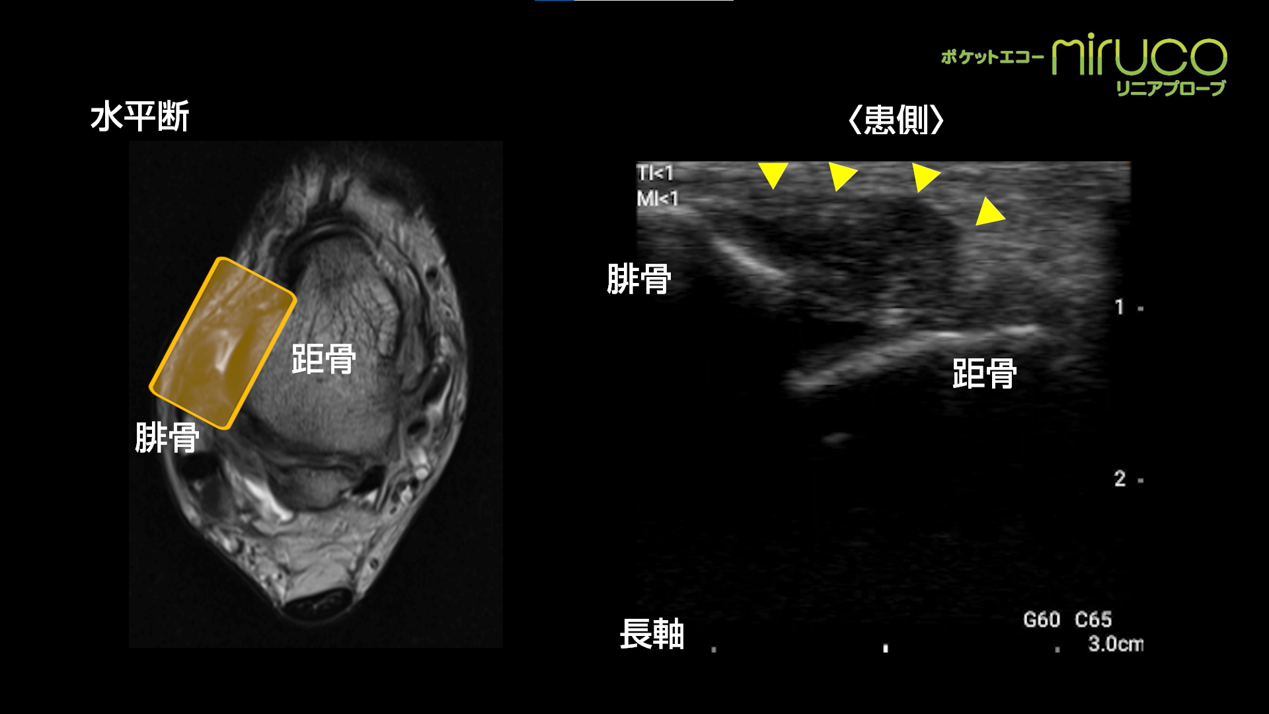

足関節捻挫と足関節靭帯損傷 り整形外科クリニック 公式 神戸市東灘区 スポーツ整形外科